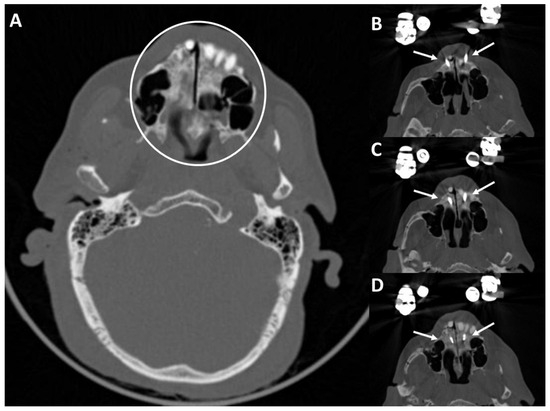

2.4. Digital Measurement of CT Scans for Analysis of Optimal Pin Insertion Angles

3.2. Results of the Digital Evaluation of the Possible Pin Insertion Areas of 100 CTs of the Skull

4.4. Evaluation of the 100 CT Scans of Healthy Subjects